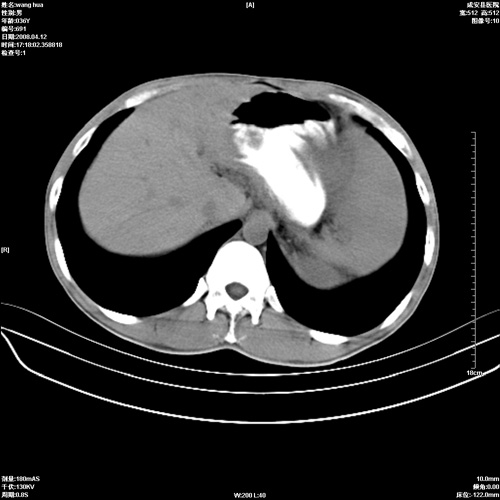

标题: CT12809:男36岁,自感上腹胀5天,B超诊断为脾肾之间占位,血 [打印本页]

标题: CT12809:男36岁,自感上腹胀5天,B超诊断为脾肾之间占位,血

请各位老师先分析一下定位 明天做增强

脾脏明显增大,其内见巨大低密度灶,境界不清,病史较短,考虑恶性病变脾血管内皮细胞肉瘤可能。建议增强扫描与脾脏淋巴瘤及血管瘤鉴别。